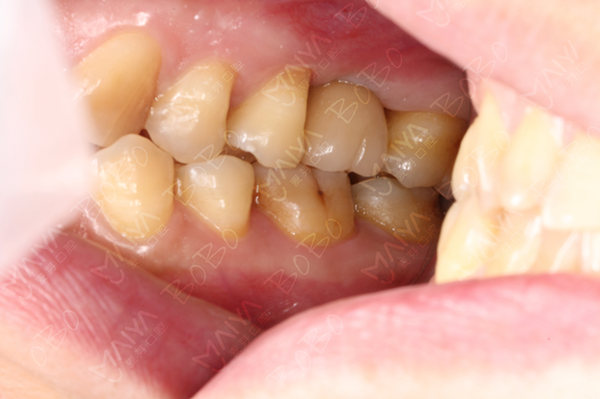

医生为许女士做口腔检查

许女士术前口腔全景片

植牙模拟判断咬合程度

种完牙后的牙齿